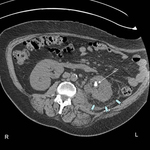

CT scan showing left ureteric calculi

From the personal collection of Dr Kasra Saeb-Parsy